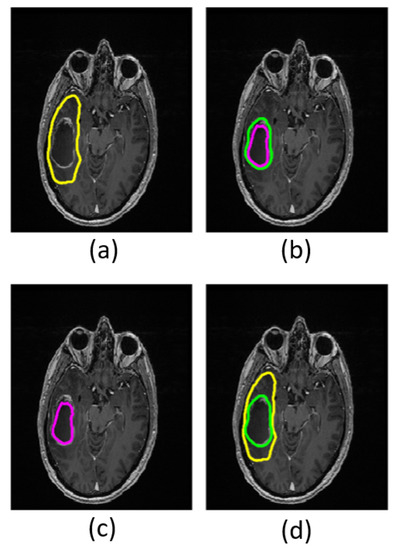

FW elimination increases FA entropy (p ≤ 0.003) and decreases FA skewness (p ≤ 0.004) in the non-enhancing regions in both low- and high-grade tumors (Table 3). Kurtosis does not decrease significantly in low-grade tumors (p = 0.90) but does decrease significantly in high-grade tumors (p ≤ 0.001). The FA distribution shifts toward higher FA values after FW correction. Refer to the Supplementary Material for a complete table of summary variables (Supplementary Material, Table S1). Maps calculated with and without FW correction are shown for a single patient in Figure 5.

Figure 5. Images and maps from a grade IV patient: (a) T1w image; (b) T2w image; (c) free-water (FW)-corrected fractional anisotropy (FAt) map; (d) non-corrected fractional anisotropy (FA) map with contours defining non-enhancing tumor; and (e) FW map. Within the non-enhancing region, more heterogeneity is revealed in the FAt map compared to the FA map. The FW map quantitatively highlights FW content.